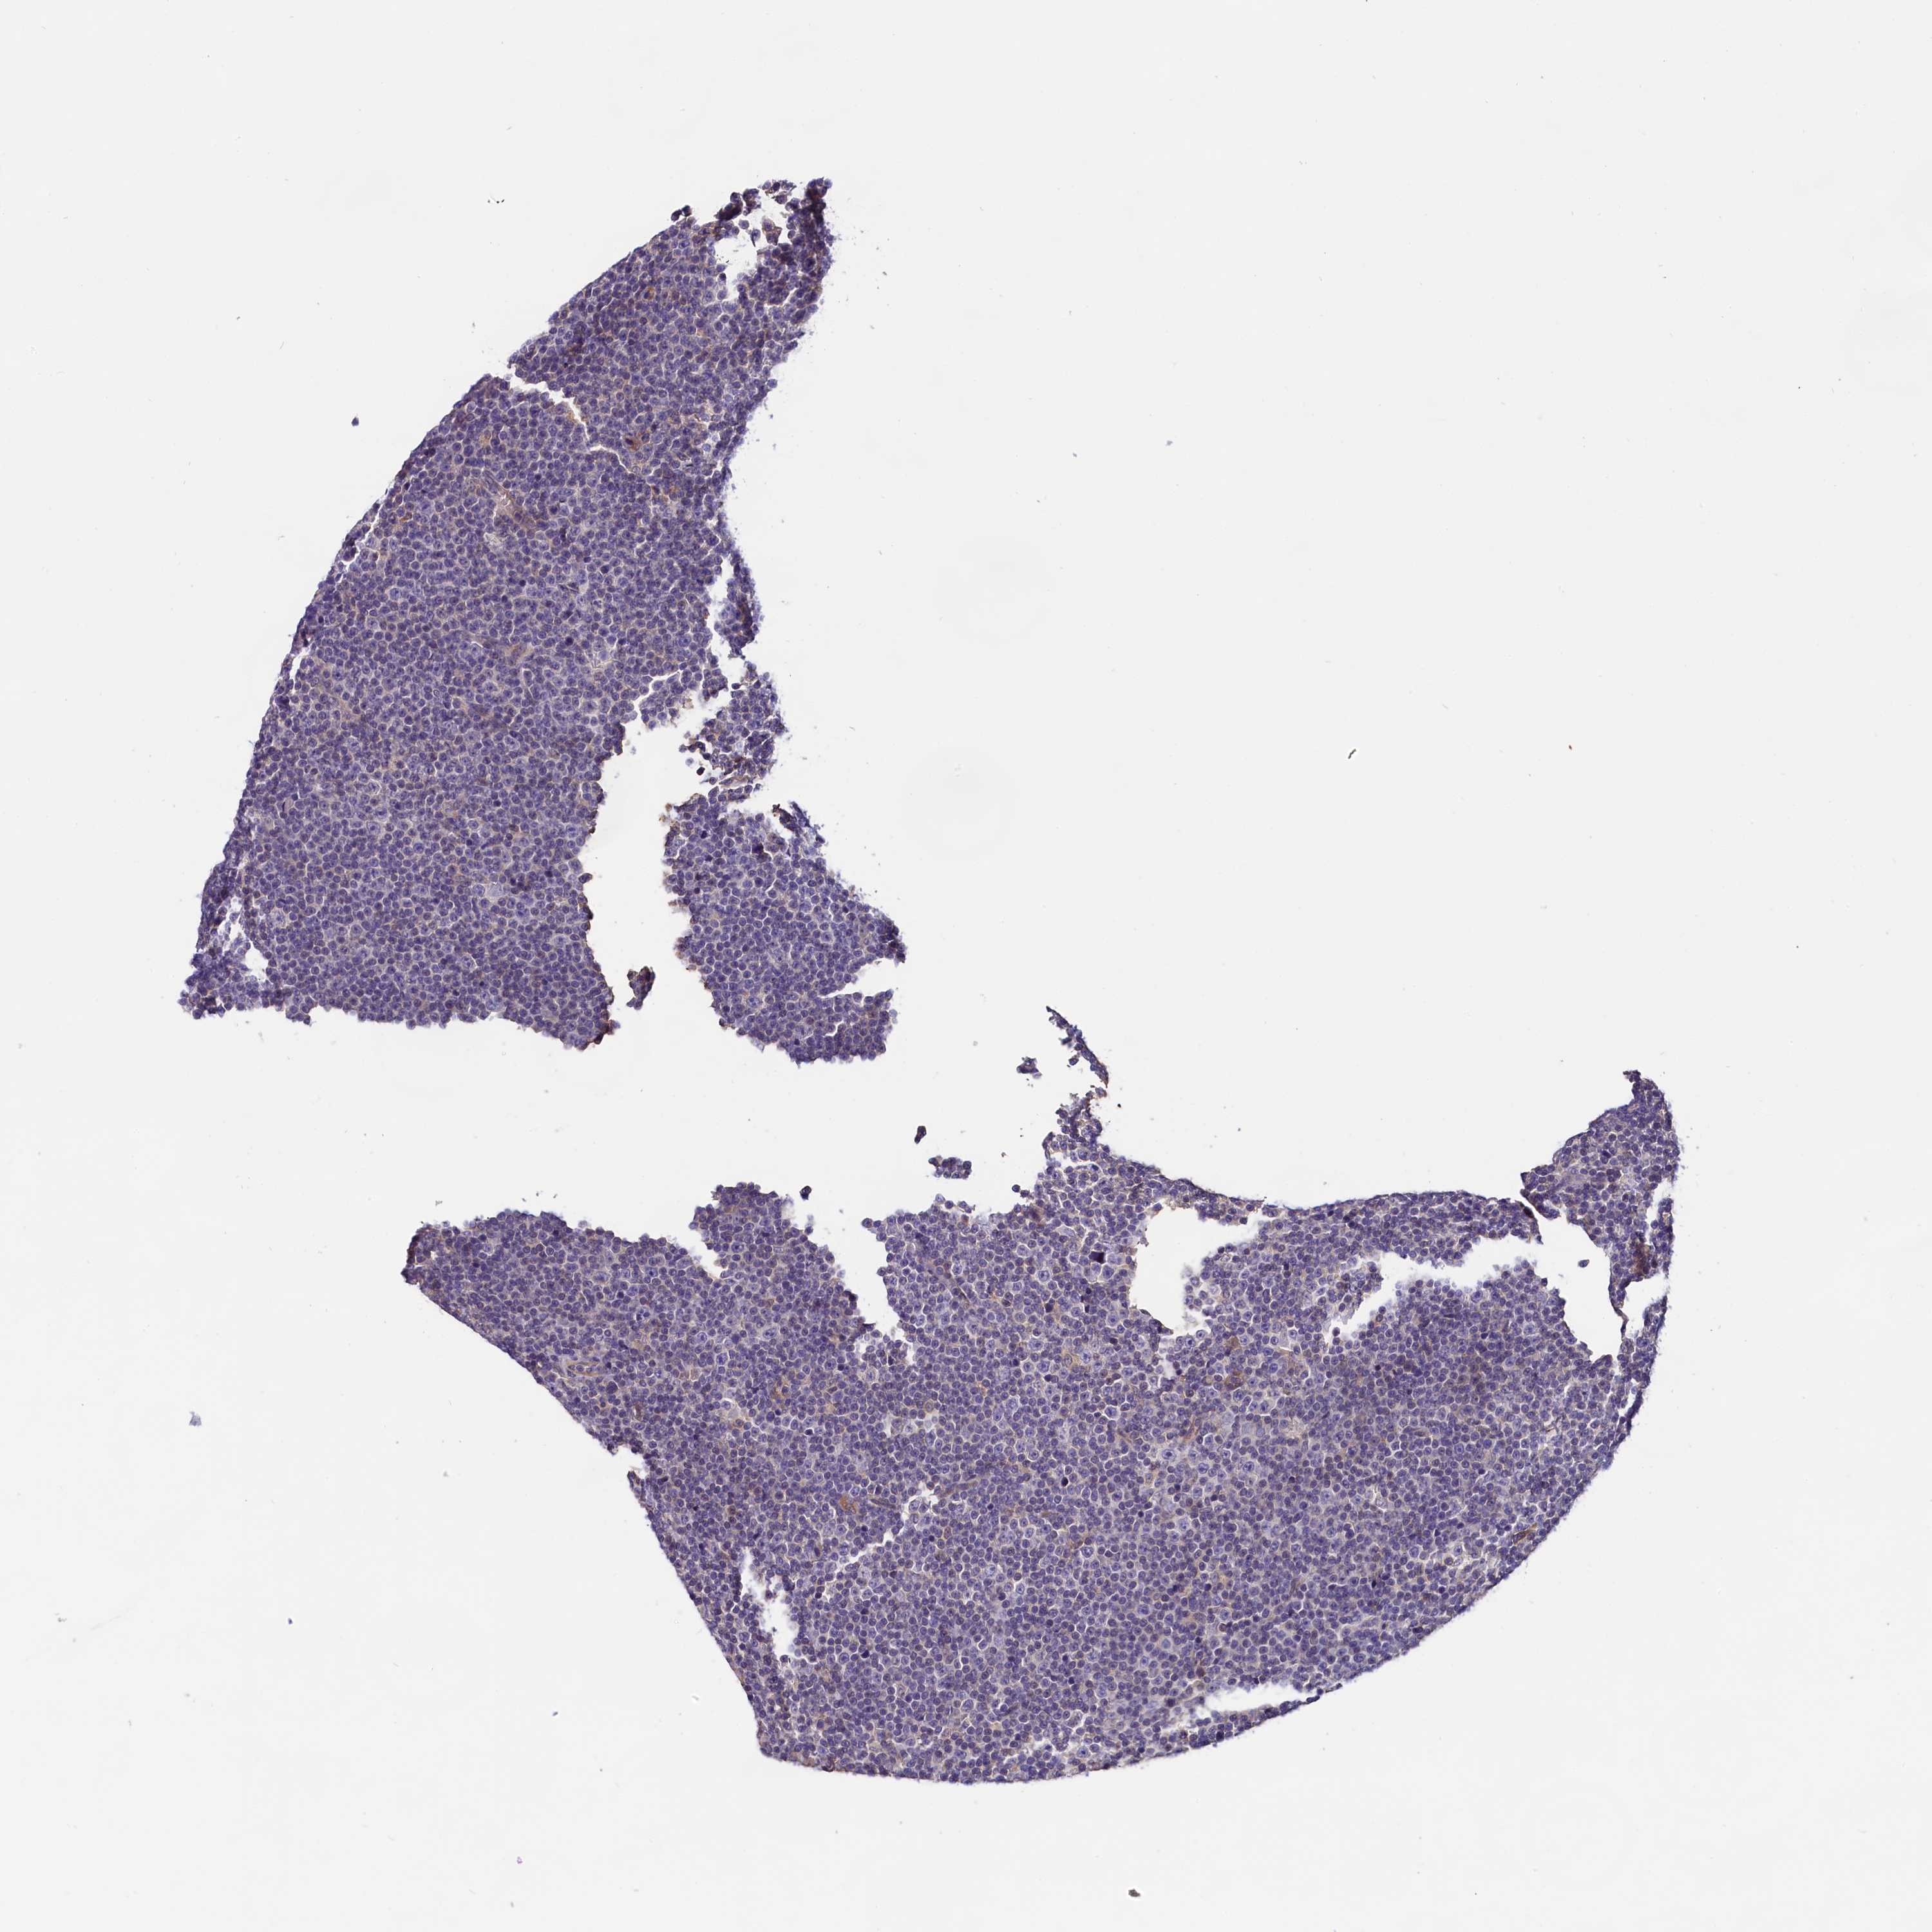

LYMPHOMA - Protein expressioni

A mouse-over function shows sample information and annotation data. Click on an image to view it in a full screen mode. Samples can be filtered based on level of antibody staining by selecting one or several of the following categories: high, medium, low and not detected. The assay and annotation is described here.

Antibody stainingi

Antibody staining in the annotated cell types in the current human tissue is reported as not detected, low, medium, or high, based on conventional immunohistochemistry profiling in selected tissues. This score is based on the combination of the staining intensity and fraction of stained cells.

Each image is clickable and will lead to virtual microscopy that enables deeper exploration of all samples and also displays staining intensity scores, fraction scores and subcellular localization as well as patient and tissue information for each sample.

Antibody HPA041253

Antibody HPA041372

Staining

High

Medium

Low

Not detected

Intensity

Strong

Moderate

Weak

Negative

Quantity

>75%

75%-25%

<25%

None

Location

Nuclear

Cytoplasmic/membranous

Cytoplasmic/membranous,nuclear

Hodgkin's disease, NOS

Malignant lymphoma, non-Hodgkin's type, Low grade

Malignant lymphoma, non-Hodgkin's type, High grade